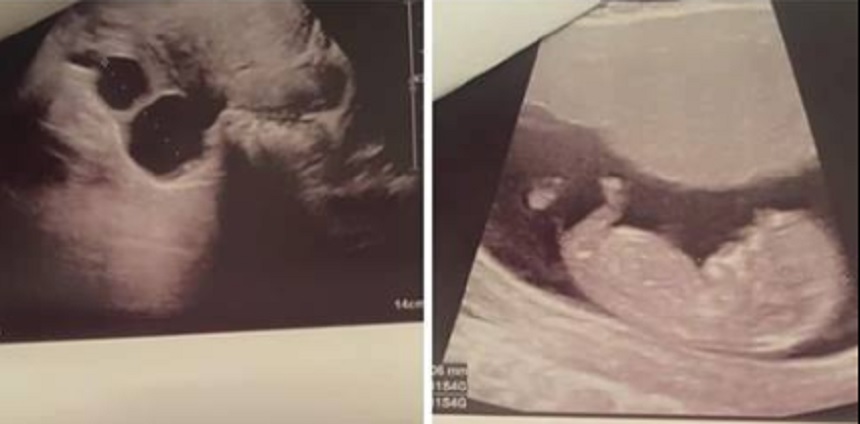

Sora Mariei Constantin este însărcinată pentru prima dată. Sursa foto: Facebook

Maria Constantin, în culmea fericirii! Au apărut imagini cu prima ecografie